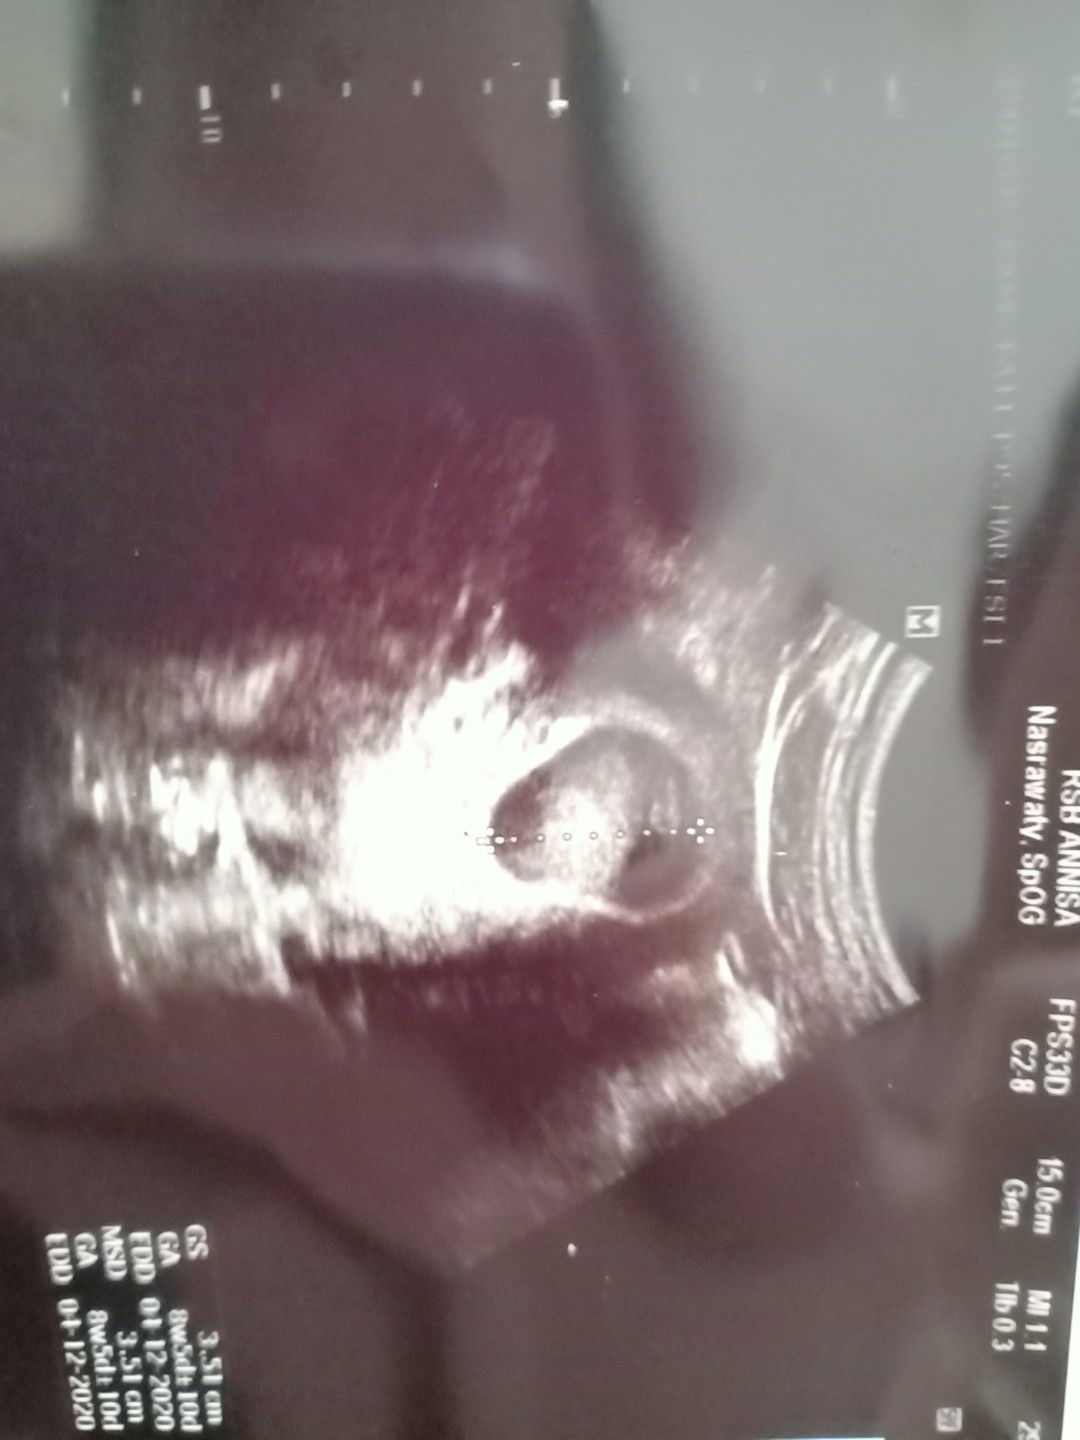

USG

Mengapa kantung kandungan saya berusia 9 minggu sedangkan janin saya masih berusia 7 minggu?